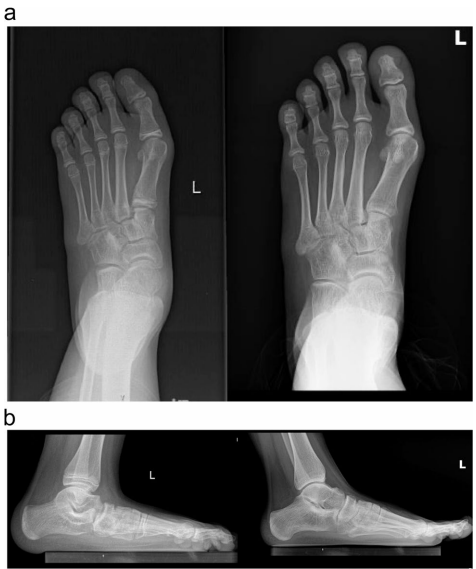

关键参数呈现两极分化改善:距跟角(TCA)减小5.48°、跟骰角(CCA)降低12.59°(均p<0.001),而跟骨倾斜角(CIA)和距骨覆盖率分别增加9.89°和10.23%,证实截骨术有效重建了足弓三维结构。典型病例影像显示(图1-3),术后距骨第1跖骨角(Meary's角)从平均6.85°显著改善。